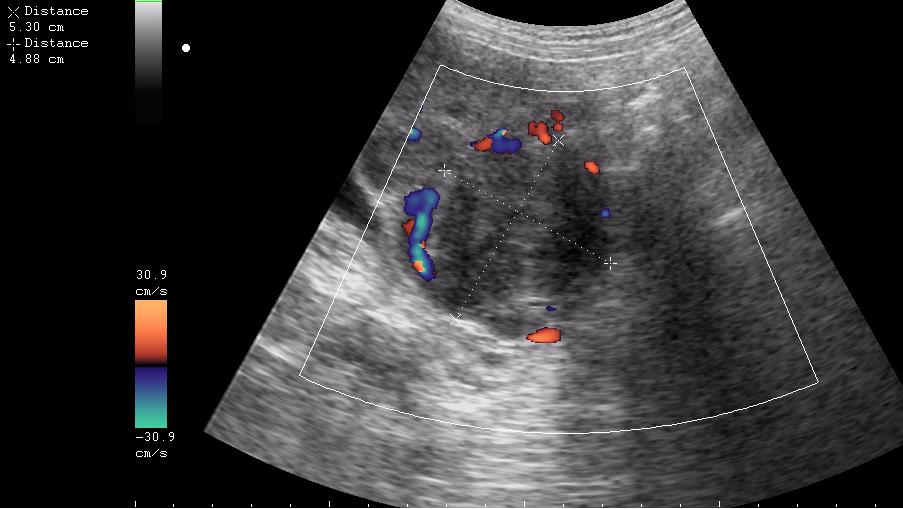

Почти как на сайте Марио,только возраст другой.Солидное гипоэхогенное негомогенное образование в области придатка слева довольно сложной структуры с усилением(?) кровотока по периферии-я за рак яичника

ещё раз - это матка 23-летней девушки. то есть, ВСЁ это, то что Вы видите, да-да, на весь экран - это матка.

Диагноз - фиброматоз. направлена строго на север и налево. к соседям. (онкодиспансер)